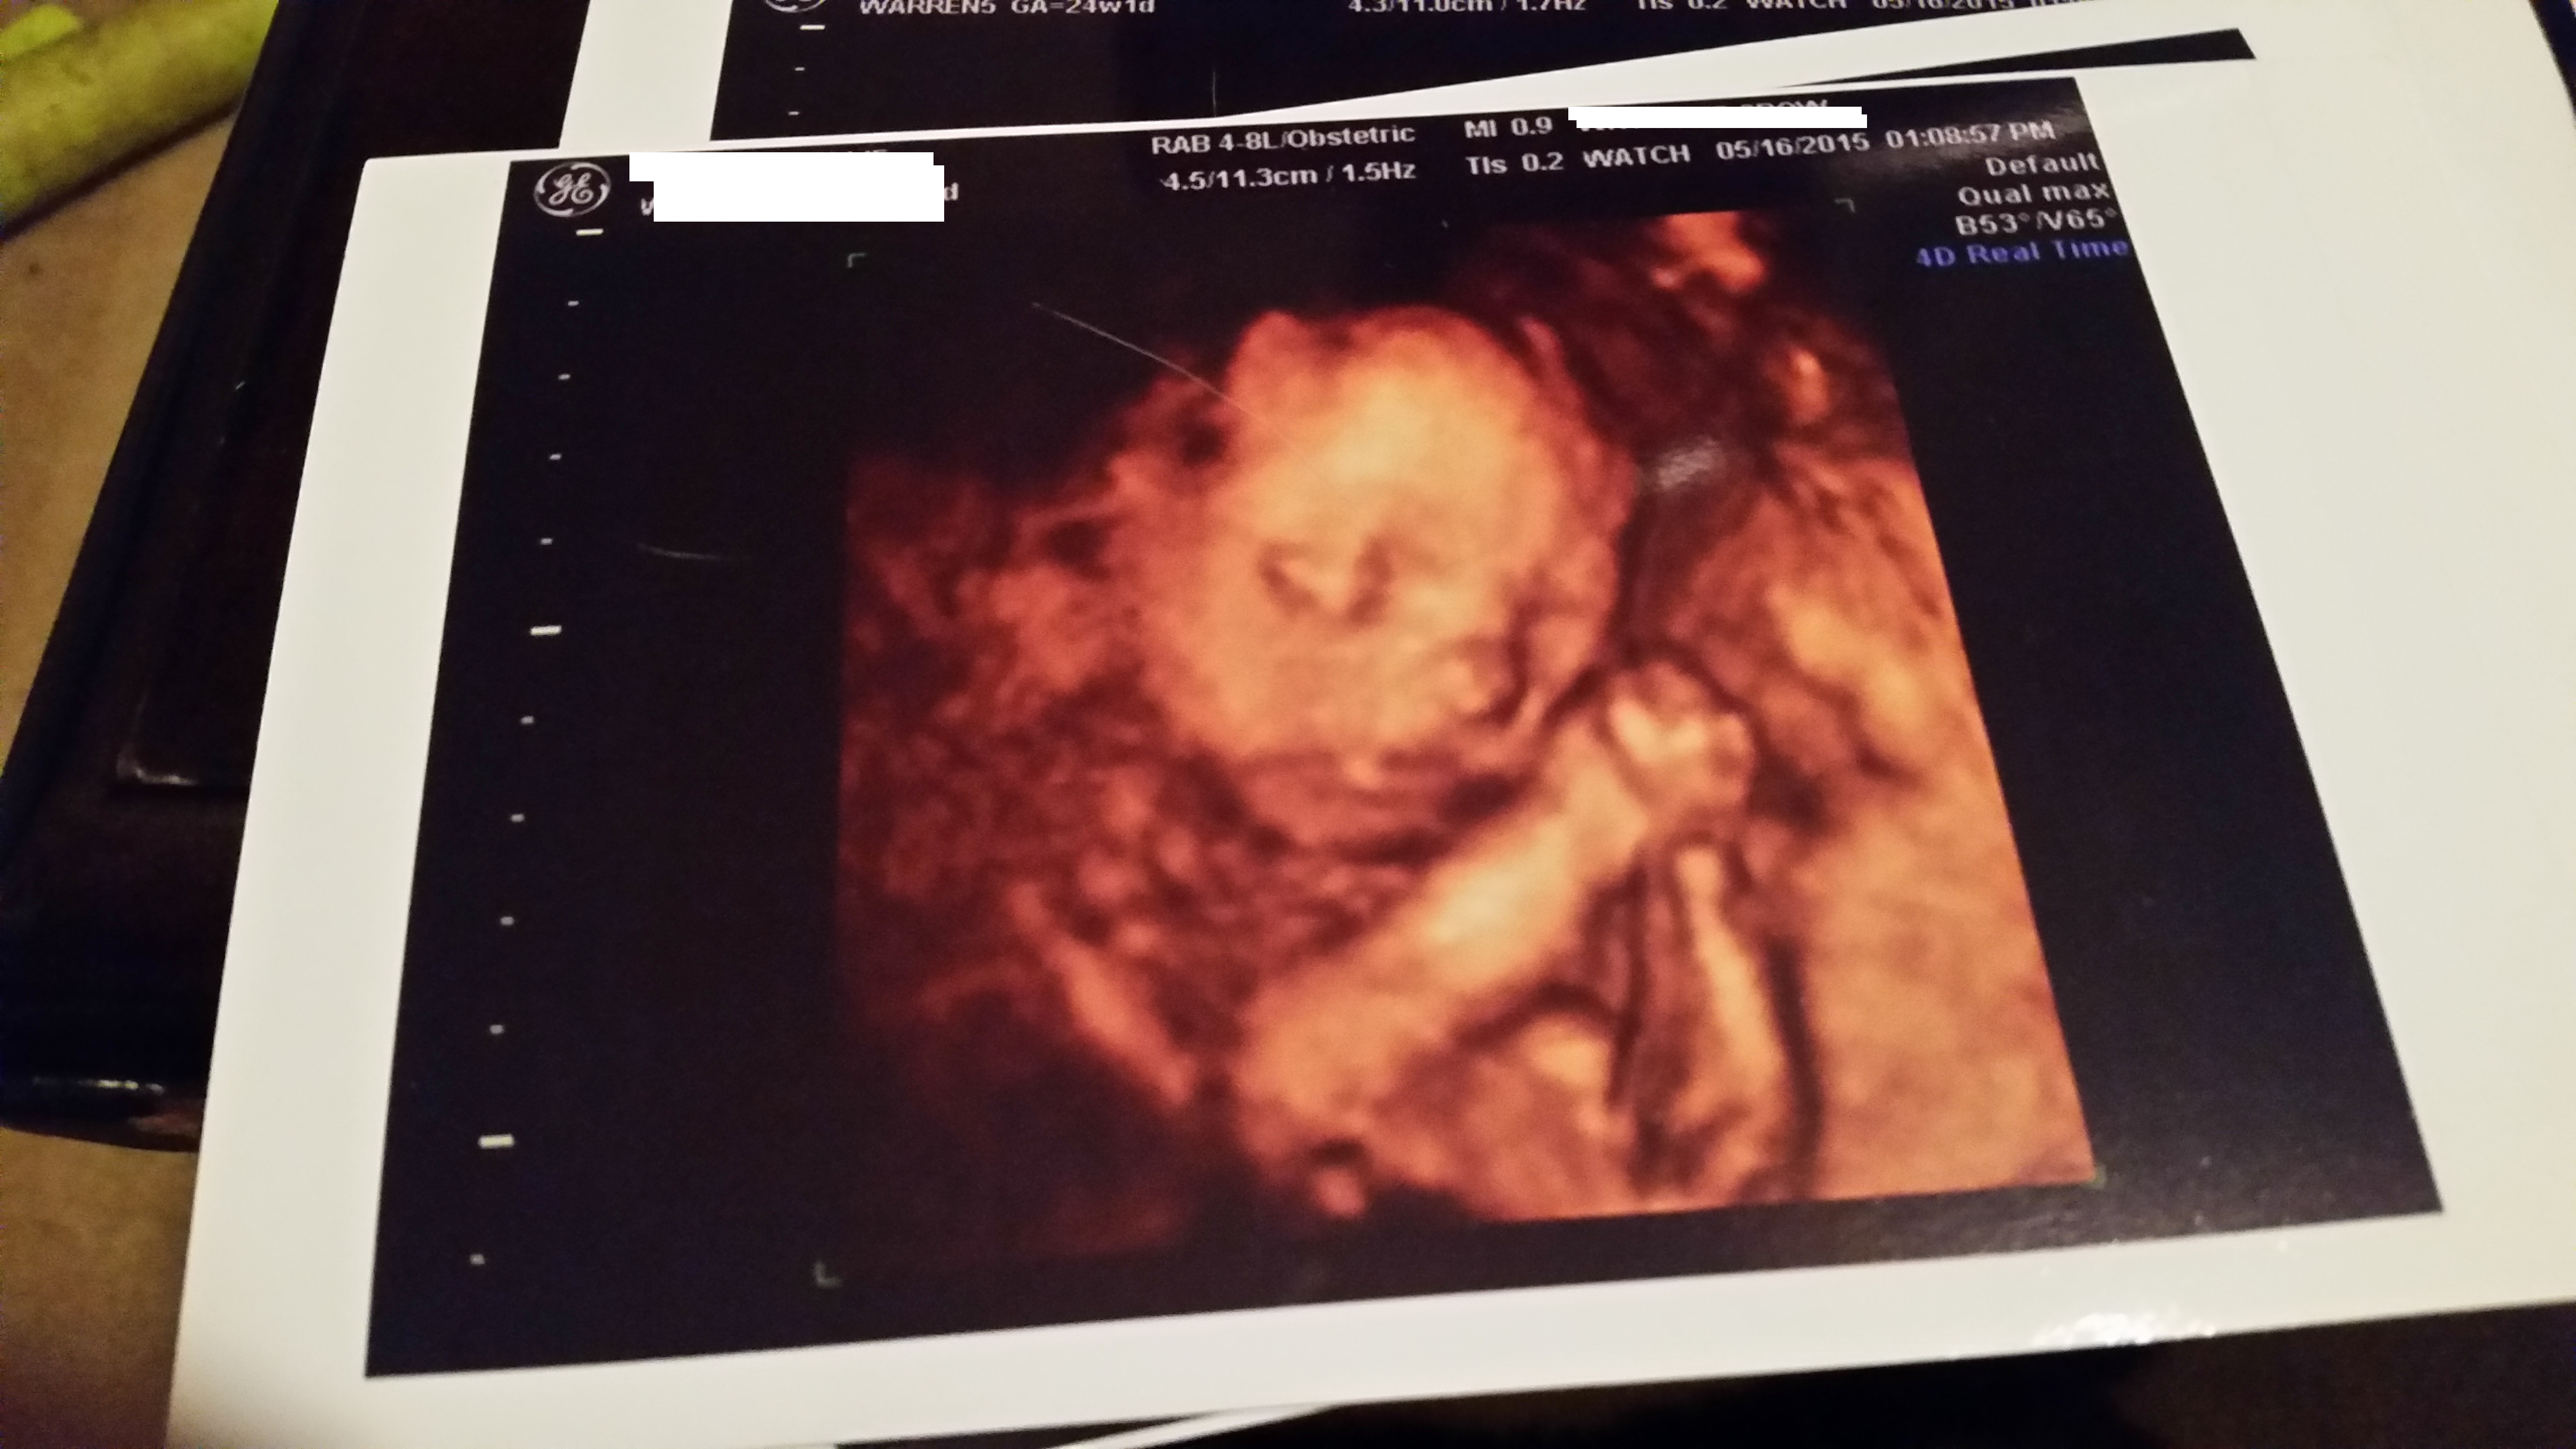

We just did it this weekend and I loved it.  We paid $140 for 25 minutes, a CD of pictures(got around 80), a DVD of little clips, and 3 4x6 pictures printed off.  They also printed off this "keepsake" which is a nicer piece of paper that describes what the baby did during the ultrasound and who all was there from the babies perspective.  We also got to book a second session for about 29 weeks with the same perks, but for only $75.  We actually did this as a Mother's Day/Father's Day gift for our parents and they loved getting to see her.

The pictures can look funny (alien-like), but I loved being able to see all of the details, right up to possibly a patch of hair that we spotted. It's amazing what all they can actually see.  We even watched her punch me and then grin!  I guess I'll have a mischievous one on my hands. Here is one of my pictures from this weekend.  I was 24w1d.